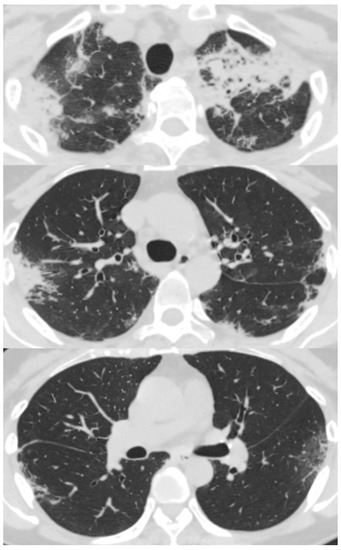

Her chest X-ray on admission showed consolidation in the bilateral peripheral-based upper lung fields and a typical radiographic pattern, i.e., “photographic negative of pulmonary edema” [3]. (Figure 1) Chest computed tomography (CT) revealed extensive ground-glass opacities in the left lung with contractile changes. Non-regional consolidation was scattered throughout the peripheral upper and middle lobes of the right lung (Figure 2).

Figure 1. Chest X-ray of 55-year-old woman upon admission with fever and dyspnea. It showed bilateral consolidation in her upper lung fields.